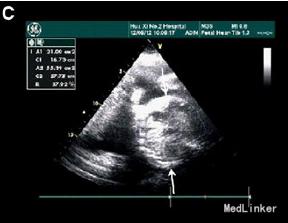

31岁女性,G2P1,孕31周,因高血压、少尿、胎儿和胎盘水肿就诊

实验室检查提示Hb 80g/L,极低的血清铁蛋白 超声提示严重腹水、心肌肥大、心包积水,羊水过多,但无皮肤水肿 轻微胸腔积水 病毒感染检查提示均为阴性 初步诊断为子痫前期、胎儿水肿和缺铁性贫血 孕妇外周血压114-138/67-92 口服降压药,注射地塞米松 入院4天出现咳嗽,不伴干湿罗音,四肢水肿加重,血压升到142-165/95-100,Hb 72g/L

孕31+4周时诱发生产 第二产程时,出现严重的呼吸困难和血压升高(177/120) 给予呋塞米静注 可见婴儿头部,故继续阴道分娩,助产 产下一男婴2200g,Apgar评分分别为2,2 胎盘巨大,重1250g 新生儿22min后死亡 尸检提示心肺衰竭死亡 最后诊断为镜像综合征